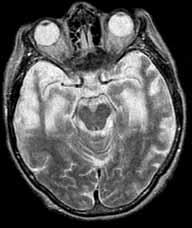

问题 一痴呆患者有明显的人格改变和行为障碍,定向力和记忆力尚好,头颅MRI T表现如图。该患者最可能的诊断为 ( )

选项 A、血管性痴呆 B、路易体痴呆 C、抑郁症 D、Pick病 E、Alzheimer病

答案 D